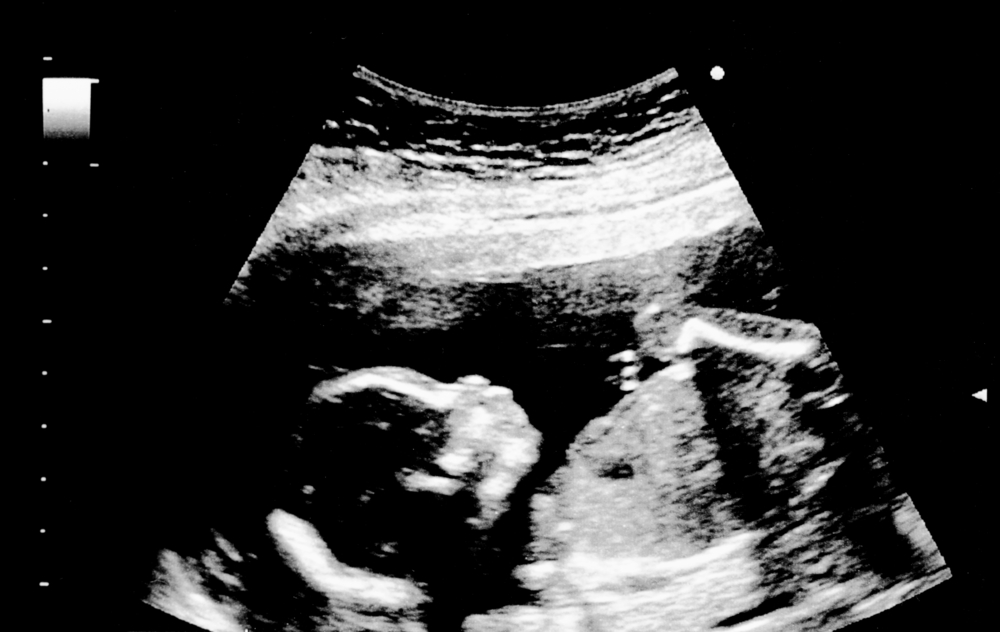

At 18 weeks, your baby’s features are still developing and moving into place. Around this time, your baby’s swallowing, sucking, hearing, and feeling reflexes are developing. Your baby will be rolling and wriggling around more now. You have to wait a few more weeks before you can notice any features on a scan.